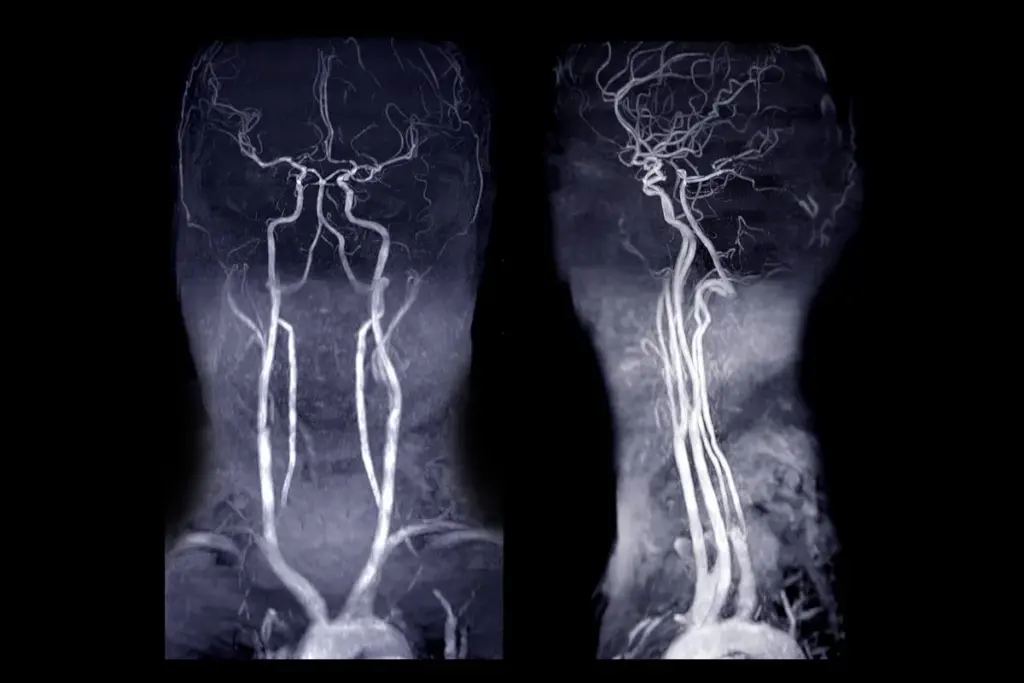

PAD MRI Detection Imaging: Capabilities and Effectiveness

MRI technology has changed how we diagnose Peripheral Artery Disease. It offers a non-invasive way to check vascular health. MRI for PAD detection is getting more attention because it gives detailed views of arteries without invasive methods or harmful radiation.

Can MRI Effectively Detect Peripheral Artery Disease?

Research shows MRI can spot Peripheral Artery Disease well. It can see the inside and outside of arteries. This is key for finding blockages and other problems linked to PAD. MRI’s clear images of arteries make it a top choice for diagnosing PAD.

Sensitivity and Specificity Rates in Clinical Studies

Studies have looked at MRI’s ability to find PAD. A study in the Journal of Vascular Surgery found MRI was 92% sensitive and 95% specific. These numbers show MRI is very good at spotting PAD.

The table below shows the results of several studies on MRI’s sensitivity and specificity for PAD detection.

Magnetic Resonance Angiography (MRA) for PAD Visualization

Magnetic Resonance Angiography (MRA) is key for seeing Peripheral Artery Disease (PAD). It’s a special MRI that looks at blood vessels. This helps doctors find and understand PAD better.

Standard MRI shows body tissues well. But MRA is made to see blood vessels. MRA techniques are optimized to highlight blood vessels, helping spot PAD problems like stenosis or blockages.

Targeting Blood Vessels with MRA

MRA uses special sequences and contrast agents to see blood vessels better. This lets doctors check the arteries closely. It’s key for finding PAD.